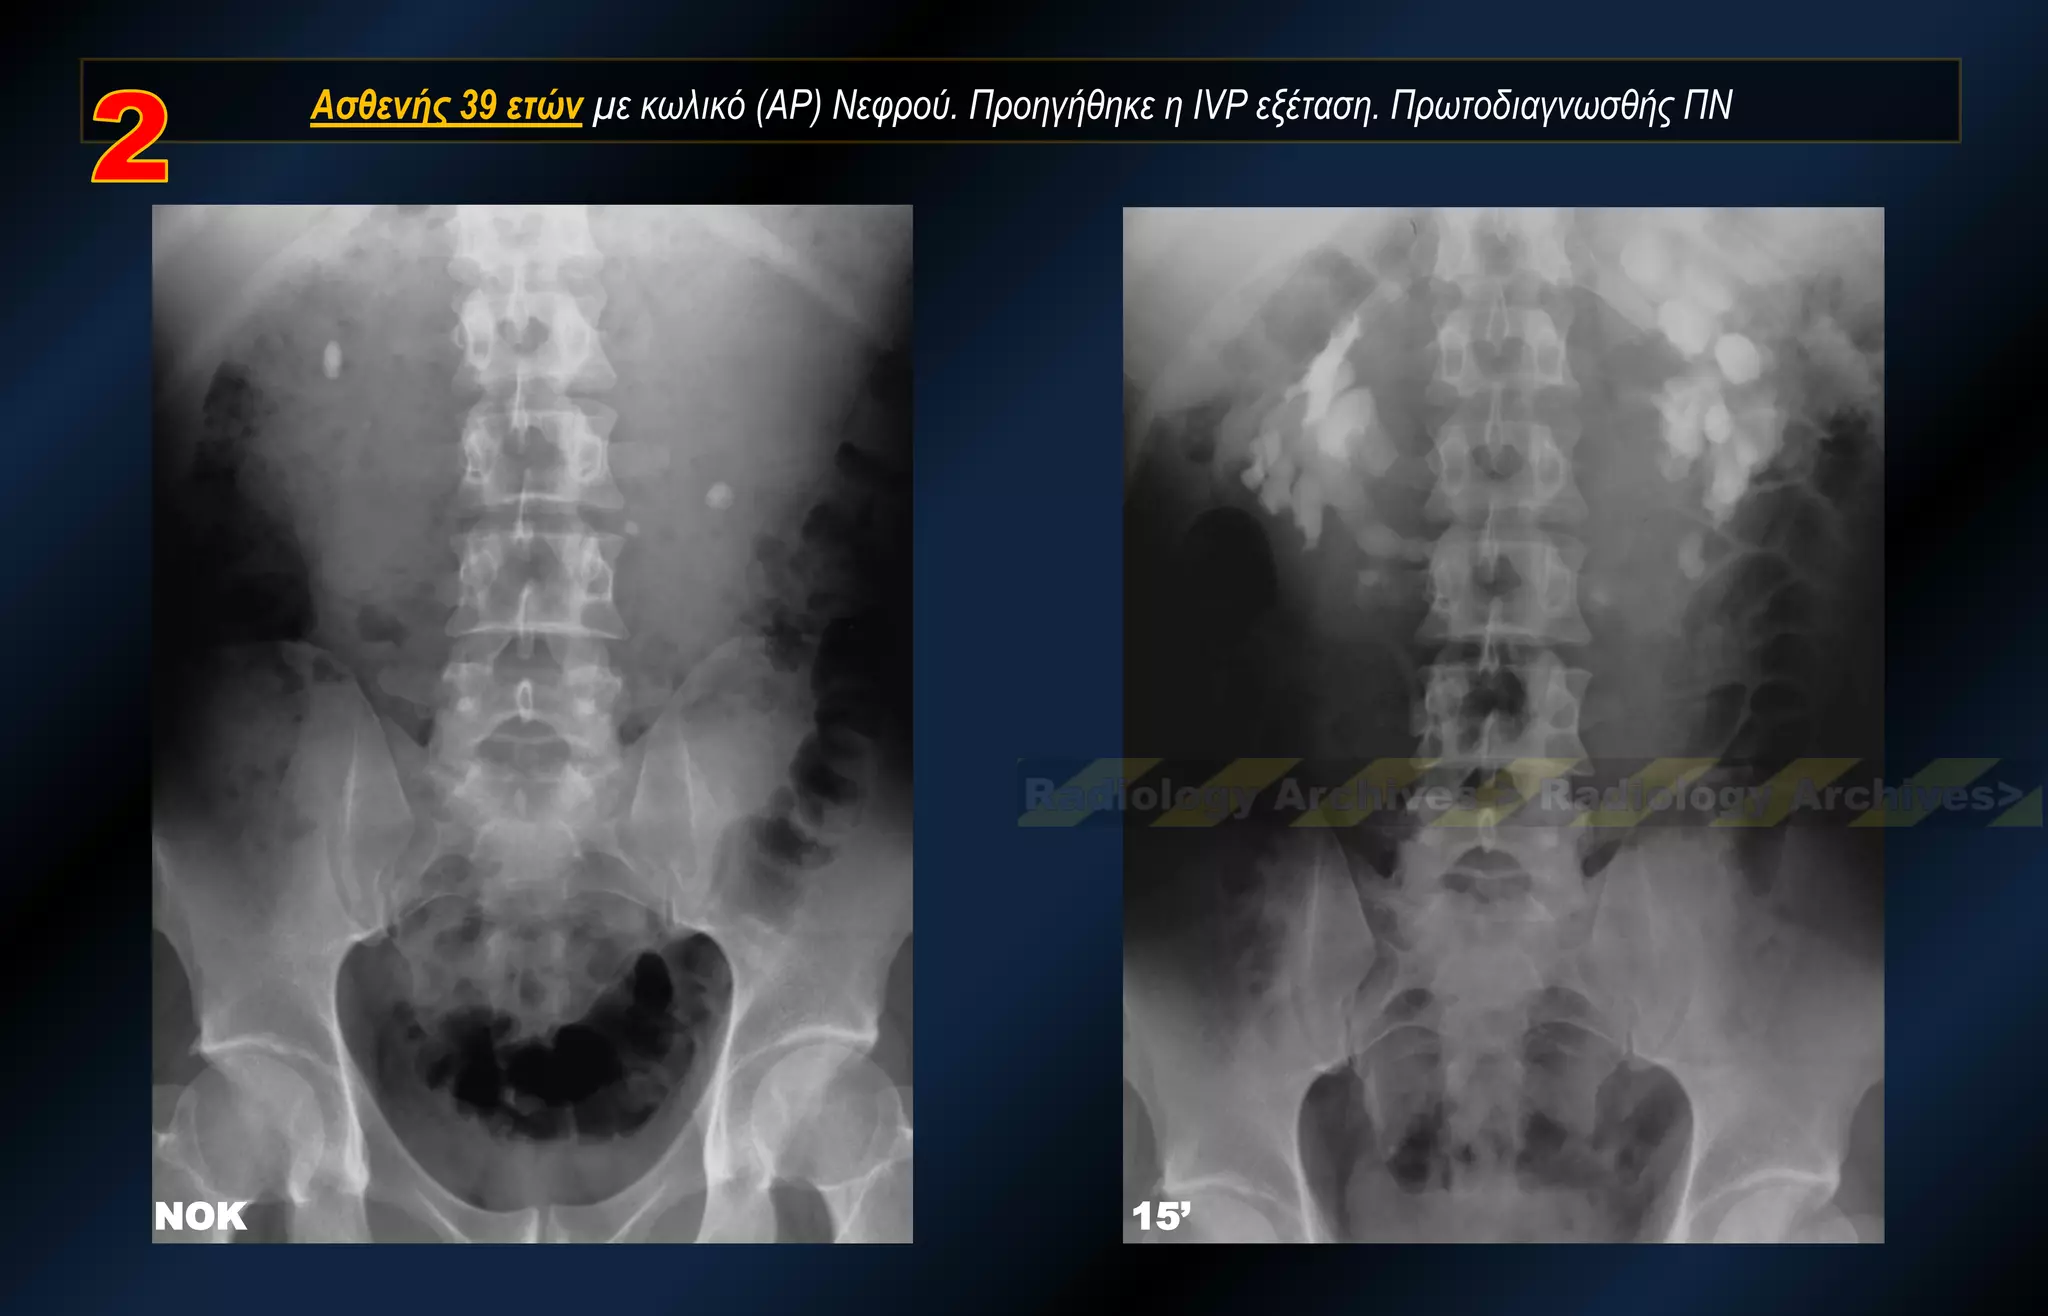

Ασθενής 39 ετών με κωλικό (ΑΡ) Νεφρού. Προηγήθηκε η IVP εξέταση. Πρωτοδιαγνωσθής ΠΝ

ΝΟΚ 15’ Ασθενής39 ετών με κωλικό (ΑΡ) Νεφρού. Προηγήθηκε η IVP εξέταση. Πρωτοδιαγνωσθής ΠΝ